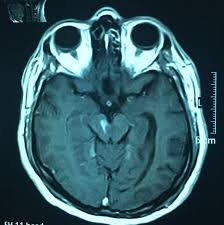

El síndrome de Weber es una condición neurológica que se caracteriza por una serie de síntomas específicos, y su aparición se debe a una lesión en una región particular del cerebro conocida como el pedículo cerebral. Este síndrome es un ejemplo interesante de cómo una lesión en una estructura cerebral específica puede tener un impacto predecible en el funcionamiento del sistema nervioso.

El pedículo cerebral, también llamado pedúnculo cerebral, es una estructura que se encuentra en la parte superior del tronco cerebral. Se compone de fibras nerviosas que conectan diferentes áreas del cerebro, incluido el tronco cerebral, con estructuras más elevadas como el tálamo y el cerebro superior.

El síndrome de Weber se produce debido a una lesión en el tracto corticonuclear, que es una vía de fibras nerviosas que conecta la corteza cerebral (la parte externa del cerebro) con los núcleos motores de los nervios craneales. Esta lesión interrumpe la comunicación entre la corteza cerebral y los núcleos motores que inervan los músculos oculares y los músculos del cuerpo.

El síndrome de Weber es el resultado de una lesión en el pedículo cerebral que conlleva parálisis oculomotora ipsolateral (parálisis de los músculos oculares del mismo lado de la lesión) debido a la afectación del tracto corticonuclear. Además, se observa hemiparesia contralateral (debilidad o parálisis en el lado opuesto del cuerpo) debido a la organización cruzada de las vías motoras en el tronco cerebral. Este síndrome es un ejemplo vívido de cómo las lesiones en regiones cerebrales específicas pueden tener efectos predecibles en la función neurológica y la coordinación motora.